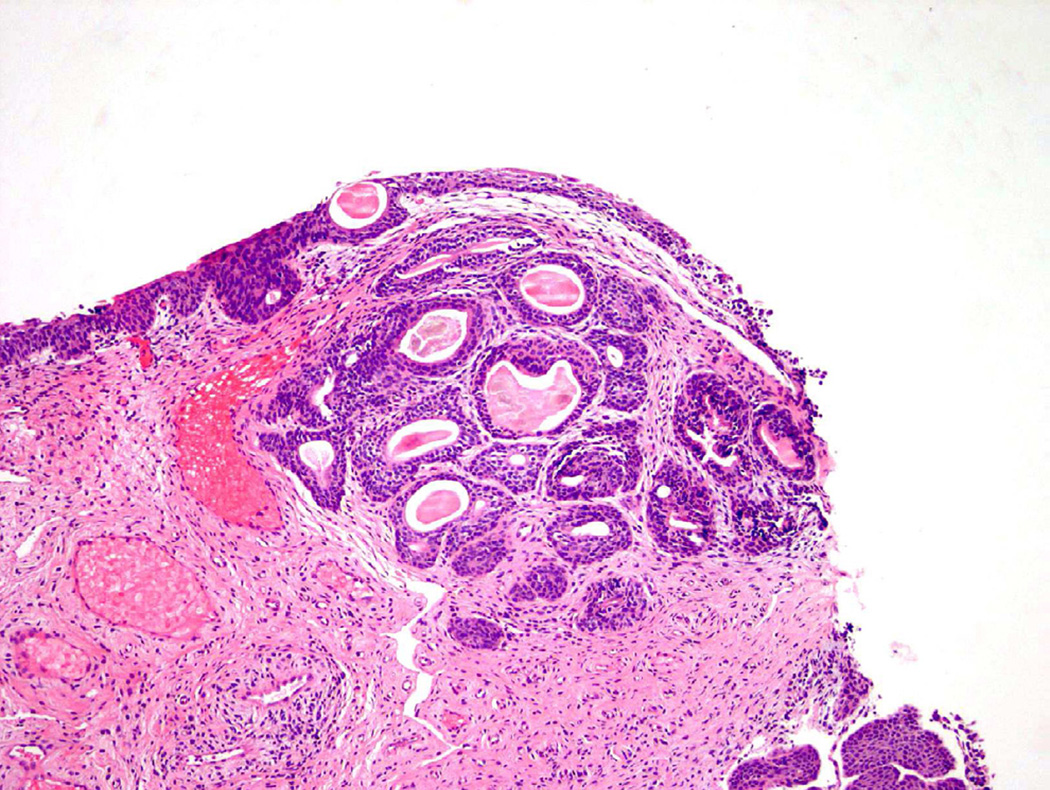

Polypoid Cystitis

Polypoid cystitis, a common variant of cystitis in the bladder, remains a challenging inflammatory lesion for pathologists and urologists alike13 (fig 7). On cystoscopy, the often exophytic growth pattern of polypoid cystitis may clinically resemble a papillary neoplasm. These lesions tend to appear in patients with a history of indwelling catheters, fistulas, chronic obstruction, or calculi. Microscopically, the lesion consists of large, bulbous outpouchings of the urothelial lining, with the lamina propria often quite edematous (Fig. 8)13. Over time, ongoing inflammation may produce scarring of the lamina propria leading to a more papillary-like appearance, as well as induce squamous metaplasia and reactive atypia14. In a 2008 study, 41 cases of polypoid cystitis that had been previously misdiagnosed as papillary urothelial neoplasia were re-reviewed13. Despite some mild atypia and mitotic figures in many of the cases, the cytologic features included uniform cell enlargement, similar vesicular chromatin patterns, and a single prominent nucleolus. Each of the 41 cases lacked definitive hyperchromasia and nuclear pleomorphism which are key criteria in differentiating benign, reactive lesions from neoplasia.

Figure 7.

Polypoid cystitis.

Figure 8.

Flat urothelial hyperplasia recognized as thickened urothelium with no atypia.